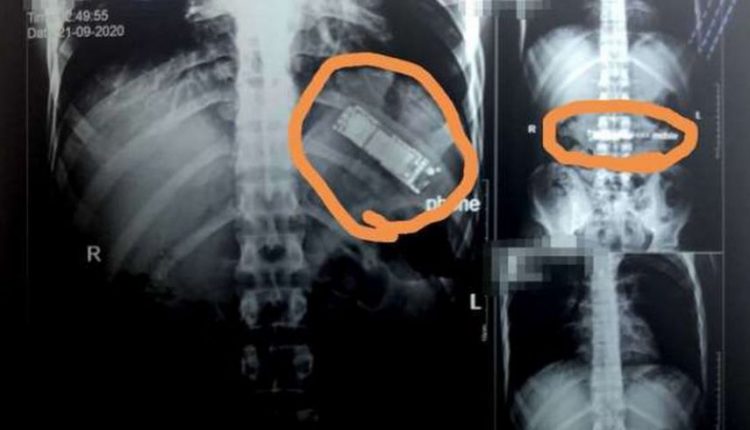

كشفت فحوص بالأشعة أجريت لمريض بمستشفيات بنها الجامعية في مصر، عن وجود هاتف محمول في معدته بقي هناك بعد أن قام بابتلاعه

منذ 7 أشهر.

وقال الدكتور محمد الجزار، استشاري أورام الصدر وأستاذ جراحة القلب والصدر والمناظير بكلية الطب في جامعة بنها،

إنه تم استقبال المريض ، من مدينة كفر شكر بالقليوبية، وتم إجراء أشعة تليفزيونية على الصدر والبطن، حيث تم اكتشاف

وجود هاتف محمول بمعدته.

وأوضح الجزار، أن المريض أكد أنه ابتلع الجهاز منذ 7 أشهر على سبيل المداعبة مع أصدقائه دون أن يعلم أي فرد من أبناء

أسرته، موضحا أنه بسؤاله عن سكوته طوال هذه الفترة، أكد أنه كان يظن أن التليفون سيخرج بمجرد حدوث استرجاع

بالمعدة مرة أخرى، إلا أن هذا لم يحدث حتى الآن.

وتابع الطبيب، أنه تم تحويل المريض لقسم الجراحة العامة بالمستشفى، ويتم إعداده حاليا ووضعه بقائمة الجراحات تمهيدا

لإجراء الجراحة سريعا والتعرف على نوع التليفون وكيفية ابتلاعه.